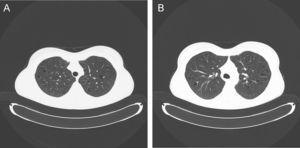

Se expone el caso de una mujer de 30 años, fumadora habitual de marihuana (34 cigarrillos/año) y de tabaco (17 paquetes/año), alérgica a la penicilina y sin otros antecedentes de interés, que consultó por disnea de esfuerzo. La exploración física era normal. En la radiografía de tórax se observaban ampollas de diferentes tamaños en ambos campos pulmonares. La tomografía computarizada (figura 1A y B) mostró ampollas enfisematosas en el ápex pulmonar bilateral, así como cambios significativos de enfisema centrolobular y panlobular con múltiples formaciones de aspecto seudoquístico en ambos pulmones, que medían desde pocos milímetros hasta 2cm de diámetro. La analítica general fue normal. La concentración de alfa-1-antitripsina era de 167mg/dl y en el test del sudor se obtuvieron valores de 40mmol/l. Los resultados de la espirometría forzada fueron los siguientes: capacidad vital forzada (FVC) de 5,08l (108%), volumen espiratorio forzado en el primer segundo (FEV 1 ) de 3,53l (95%) y FEV 1 /FVC de 0,69. La prueba broncodilatadora fue negativa. Se determinaron los volúmenes pulmonares ¿capacidad pulmonar total de 6,80l (113%), capacidad funcional residual de 3,79l (124%) y volumen residual 1,68l (97%)¿ y la difusión pulmonar ¿capacidad de difusión de monóxido de carbono del 79% y relación capacidad de difusión de monóxido de carbono/volumen alveolar del 110%¿.

Figura 1. (A y B). Imagen de tomografía computarizada (TC) en la que se observan ampollas enfisematosas bilaterales y cambios significativos de enfisema centrolobular y panlobular con múltiples formaciones de aspecto pseudoquístico en ambos pulmones que miden desde pocos milímetros hasta 2cm de diámetro.